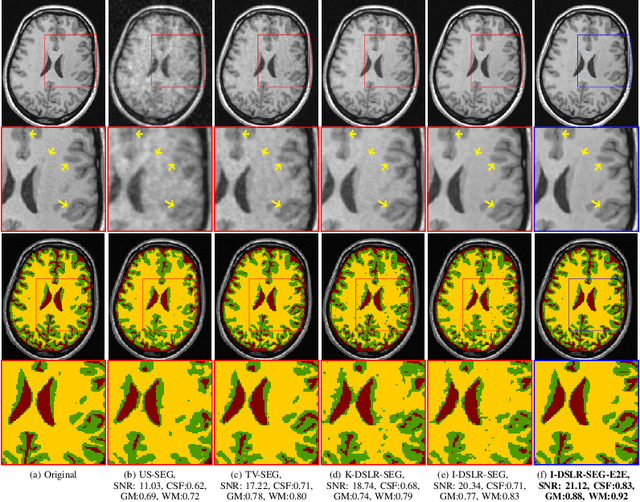

Abstract:The volume estimation of brain regions from MRI data is a key problem in many clinical applications, where the acquisition of data at high spatial resolution is desirable. While parallel MRI and constrained image reconstruction algorithms can accelerate the scans, image reconstruction artifacts are inevitable, especially at high acceleration factors. We introduce a novel image domain deep-learning framework for calibrationless parallel MRI reconstruction, coupled with a segmentation network to improve image quality and to reduce the vulnerability of current segmentation algorithms to image artifacts resulting from acceleration. The combination of the proposed image domain deep calibrationless approach with the segmentation algorithm offers improved image quality, while increasing the accuracy of the segmentations. The novel architecture with an encoder shared between the reconstruction and segmentation tasks is seen to reduce the need for segmented training datasets. In particular, the proposed few-shot training strategy requires only 10% of segmented datasets to offer good performance.

Abstract:The main focus of this work is a novel framework for the joint reconstruction and segmentation of parallel MRI (PMRI) brain data. We introduce an image domain deep network for calibrationless recovery of undersampled PMRI data. The proposed approach is the deep-learning (DL) based generalization of local low-rank based approaches for uncalibrated PMRI recovery including CLEAR [6]. Since the image domain approach exploits additional annihilation relations compared to k-space based approaches, we expect it to offer improved performance. To minimize segmentation errors resulting from undersampling artifacts, we combined the proposed scheme with a segmentation network and trained it in an end-to-end fashion. In addition to reducing segmentation errors, this approach also offers improved reconstruction performance by reducing overfitting; the reconstructed images exhibit reduced blurring and sharper edges than independently trained reconstruction network.